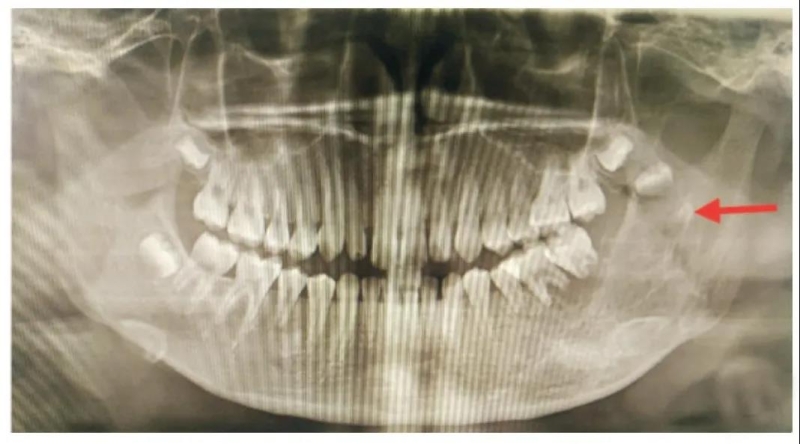

造成出血的原因有很多,其中一种情况非常凶险,就是牙槽血管瘤、 颌骨中心性血管瘤。

患者一般无明显症状,有的患者,尤其是青少年,在牙龈上长了一个松软的、暗红色的肿物,一碰就出血,尤其是搏动性出血!并且邻近的牙齿松动,就要小心颌骨中心性血管瘤!这是一种非常凶猛的疾病,别说拔除患牙, 就算洗牙,都会导致非常严重的大出血,危及生命。

9)肿瘤区域内的牙齿,例如恶性肿瘤、颌骨中央性血管瘤等,不能拔牙。